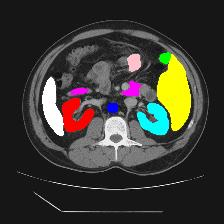

Medical image segmentation is one of the most fundamental tasks concerning medical information analysis. Various solutions have been proposed so far, including many deep learning-based techniques, such as U-Net, FC-DenseNet, etc. However, high-precision medical image segmentation remains a highly challenging task due to the existence of inherent magnification and distortion in medical images as well as the presence of lesions with similar density to normal tissues. In this paper, we propose TFCNs (Transformers for Fully Convolutional denseNets) to tackle the problem by introducing ResLinear-Transformer (RL-Transformer) and Convolutional Linear Attention Block (CLAB) to FC-DenseNet. TFCNs is not only able to utilize more latent information from the CT images for feature extraction, but also can capture and disseminate semantic features and filter non-semantic features more effectively through the CLAB module. Our experimental results show that TFCNs can achieve state-of-the-art performance with dice scores of 83.72\% on the Synapse dataset. In addition, we evaluate the robustness of TFCNs for lesion area effects on the COVID-19 public datasets. The Python code will be made publicly available on https://github.com/HUANGLIZI/TFCNs.